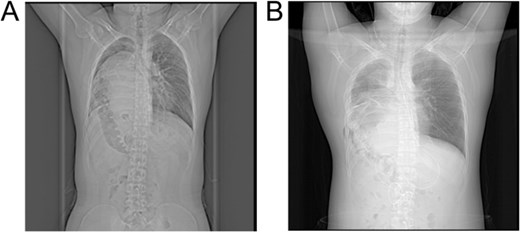

On postoperative day 3, a follow-up CT scan indicated atelectasis in the right lung due to compression, with displacement of the cardiac silhouette to the left and a small pleural effusion in the right thoracic cavity. The patient participated in lung capacity exercises and chest physiotherapy, gradually recovering respiratory function. Within one week post-surgery, the patient showed significant improvement, with marked relief from dyspnea symptoms. CT imaging demonstrated satisfactory re-expansion of the right lung, and the liver had returned to the abdominal cavity, showing substantial morphological improvement compared to preoperative images (Fig. 3A and B). At a 3-month follow-up, the patient remained asymptomatic, and imaging revealed no recurrence of the hernia or other complications.

X-ray images: (A) Preoperative X-ray showing a suspected liver mass occupying the right thoracic cavity; (B) Postoperative X-ray showing re-expansion of the right lung and the liver returned to the abdominal cavity.